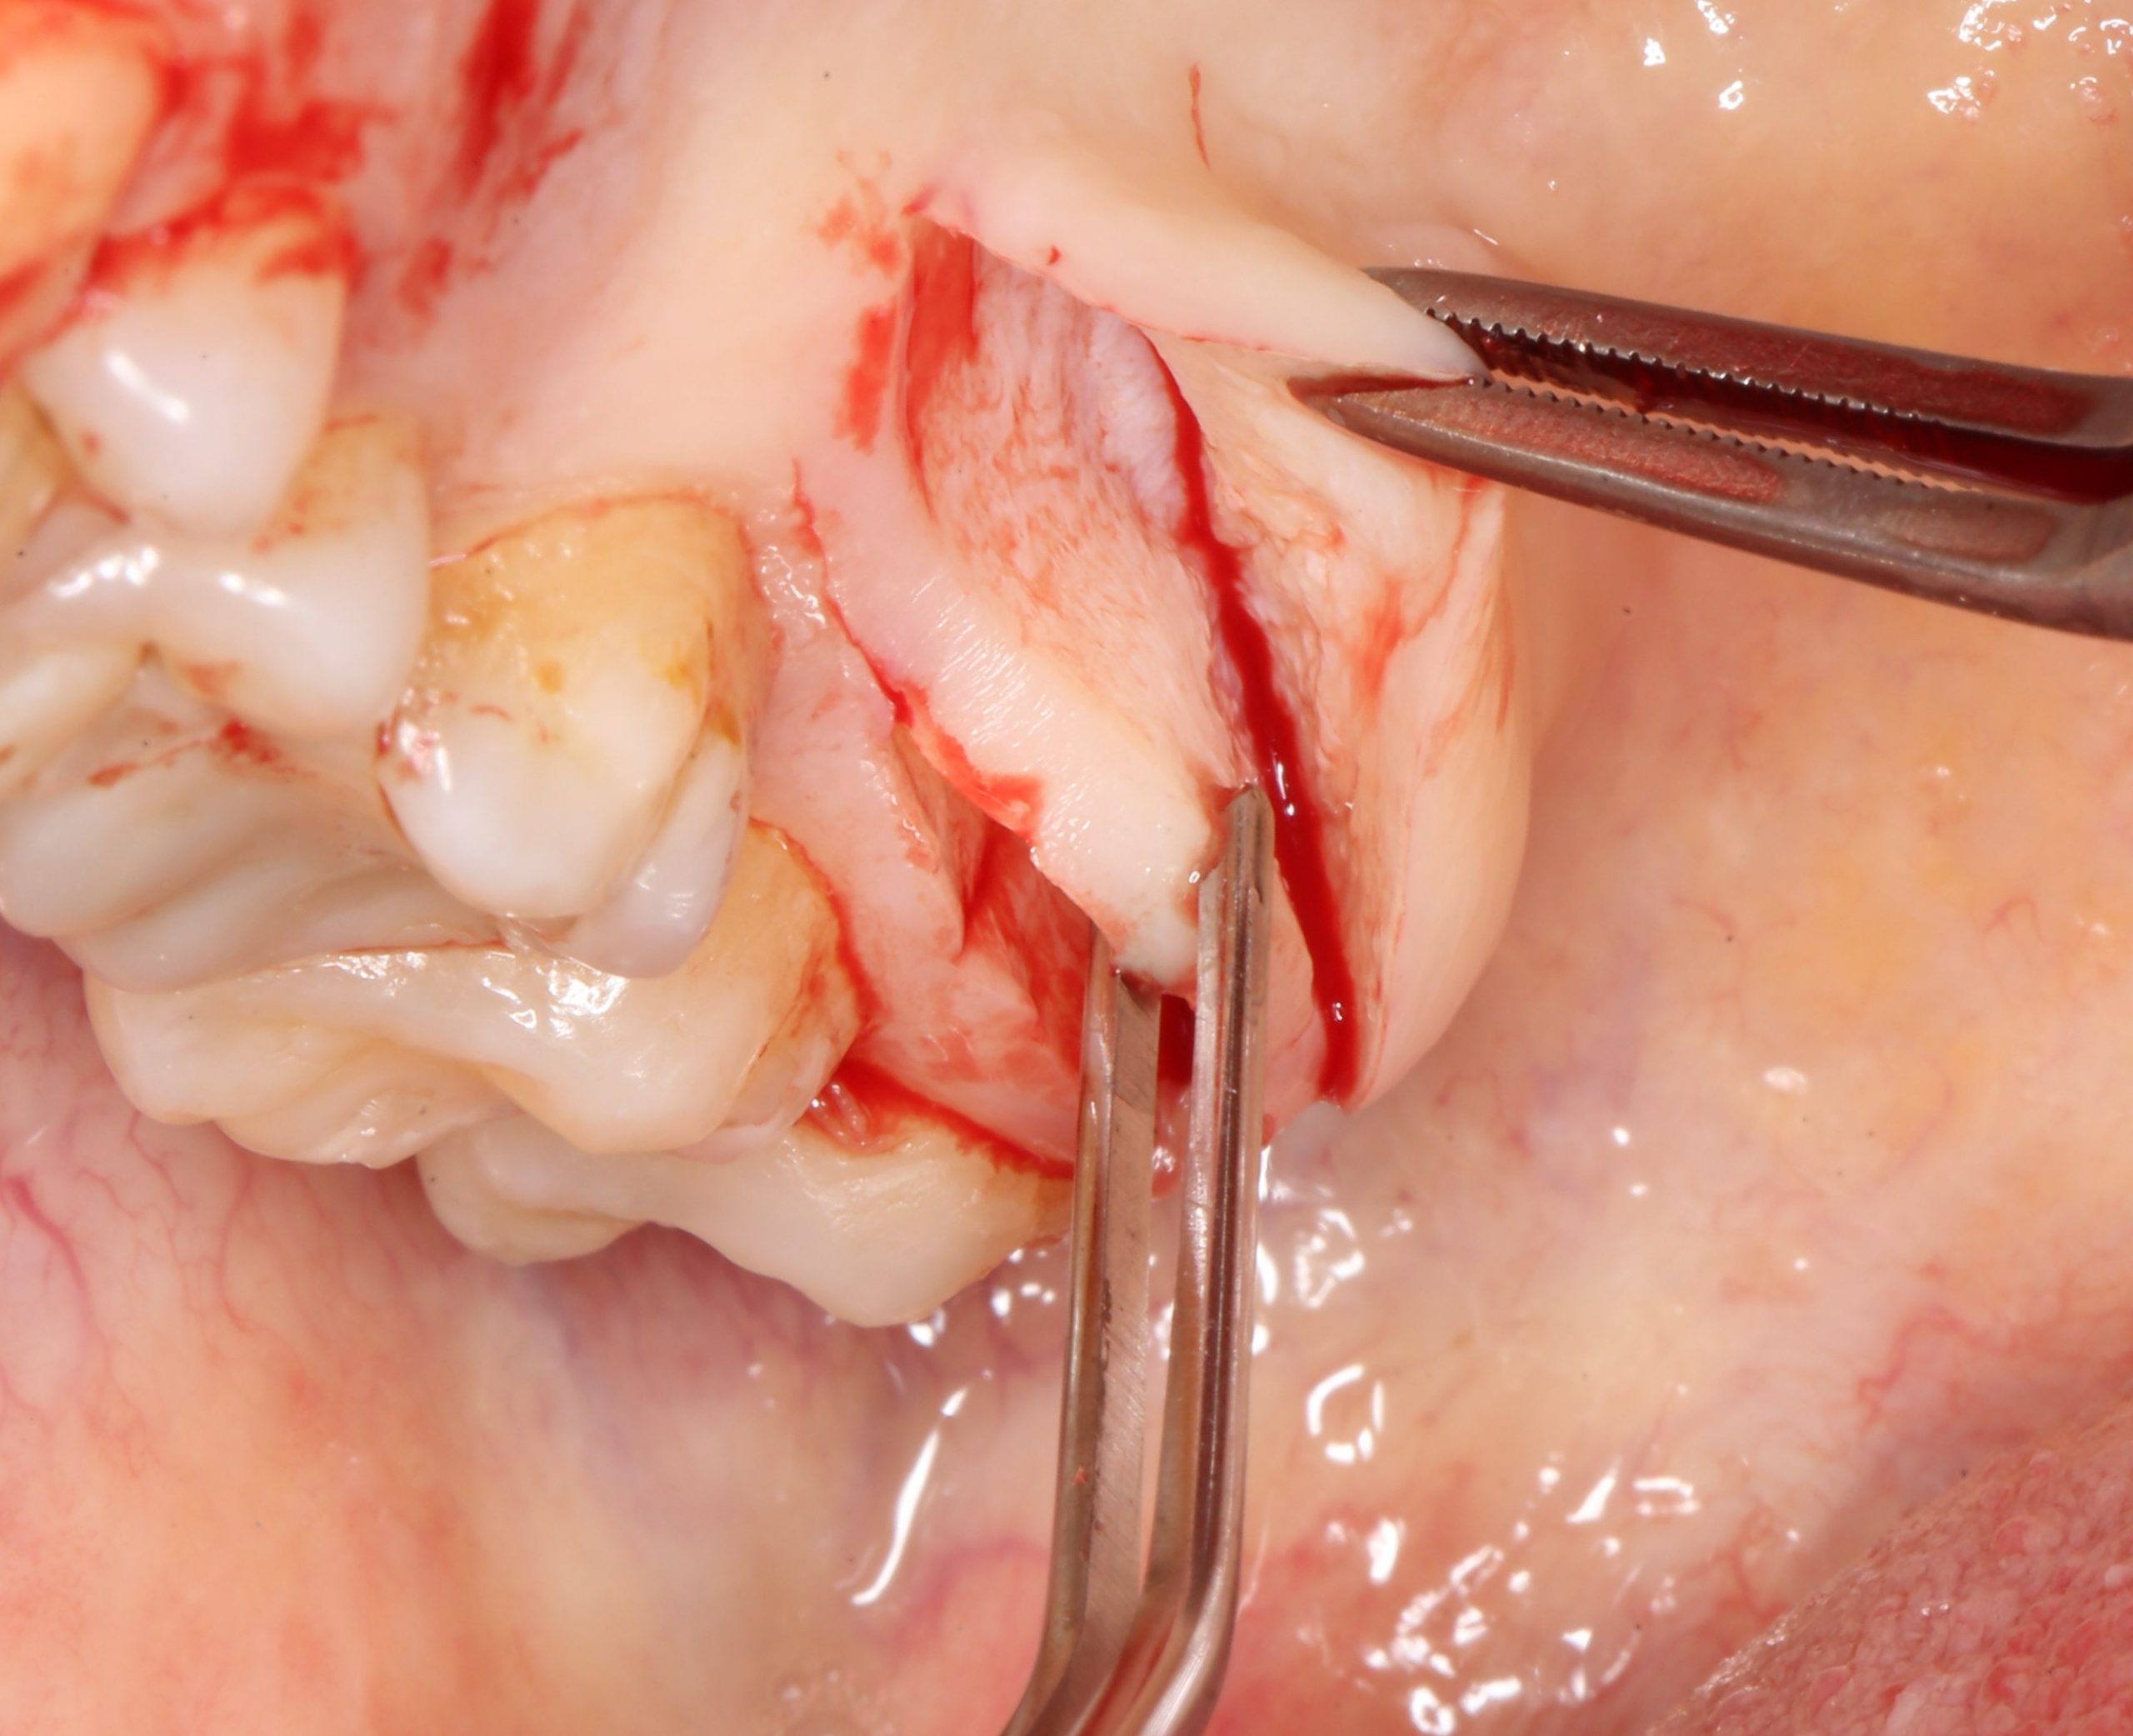

Следующий шаг — подготовка ложа под соединительнотканный аутотрансплантат или, проще говоря — под пересадку десны. Мы решили минимизировать травму, поэтому будем создавать подслизистый тоннель:

Это довольно просто, хотя и требуется известная аккуратность. Мы используем обычные инструменты для синуслифтинга:

Вы уже догадались, что мы не планируем дополнительных разрезов — весь объём работы мы проведём через лунки зубов. Таким образом, мы снизим травматичность нашей операции и, как следствие, риск возможных осложнений.

В качестве донорского участка мы выбираем отдел твёрдого нёба ближе к бугру верхней челюсти. Забор аутотрансплантата осуществляется методом расщепления:

При подходящих условиях и правильной реализации, это довольно комфортная для пациента методика получения аутотрансплантатов. При этом, они просты в обработке и почти деэпителизированы — нужно снять лишь тонкий слой эпителия «с торца» трансплантата: